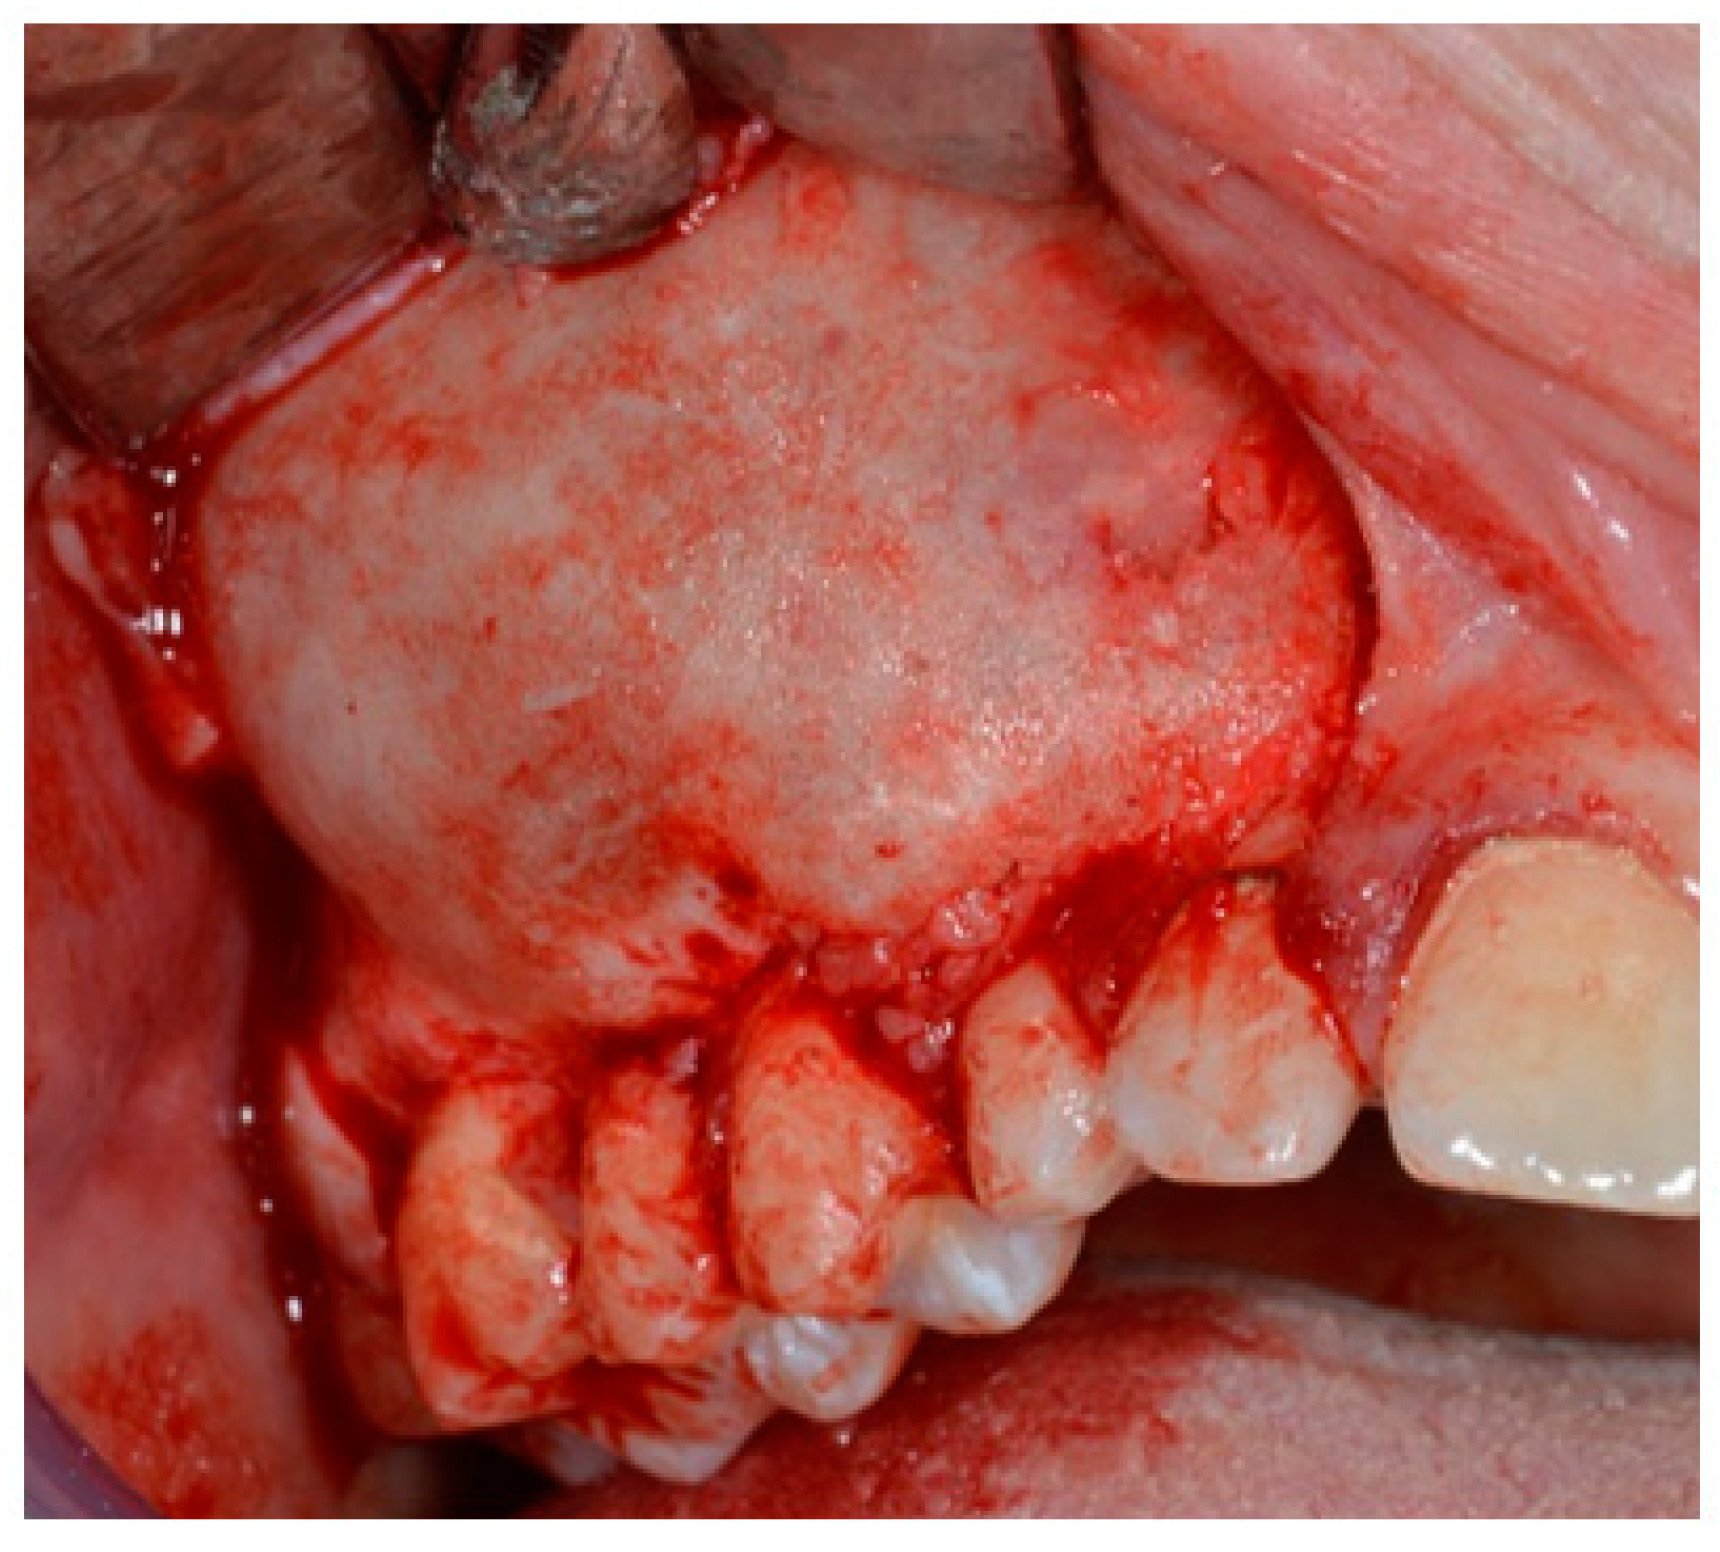

The AOT case refers to 2018 when a 14-year-old male patient was referred to the Department of Oral and Maxillo-Facial Sciences of the Sapienza University of Rome with pain and swelling in the right maxilla. Clinical examinations showed a single 4 × 4 cm swelling on the labial aspect of the right maxillary alveolus in relation to teeth 12 to 17. The overlying mucosa was normal (Figure 1). On palpation, the swelling was bony, hard and non-tender. Radiographic examinations such as panoramic X-ray and computed tomography scan (Figure 2) showed a demarcated unilocular radiolucent lesion extending from 1.2 to 1.7 with a permanent canine embedded within the lesion and pushed away from its normal position. The possibilities of follicular cyst or odontogenic tumor were considered clinically.

Figure 1. Expansion of buccal cortical bone.